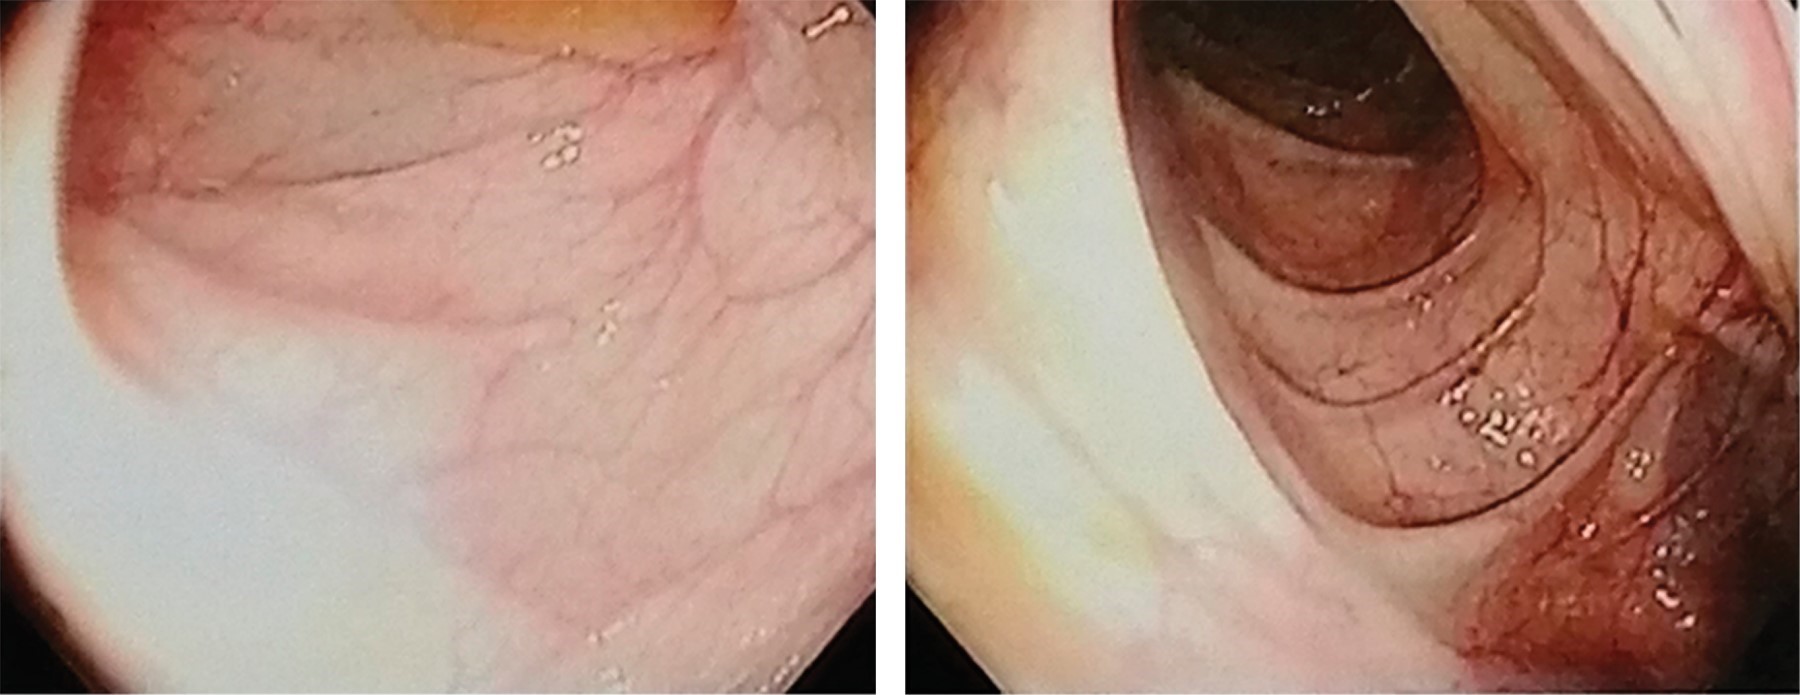

Paciente femenino de 25 años de edad, originaria y residente de Hermosillo, Sonora, México. Inició padecimiento desde el nacimiento con infecciones respiratorias recurrentes en número mayor de ocho en un año, sin presentar infecciones respiratorias graves. Se estudió por diarrea crónica sin etiología definida por gastroenterología, en mayo de 2012 se agudizó la sintomatología al presentar evacuaciones disminuidas en consistencia hasta en 15 eventos al día, dolor epigástrico y rectorragia. Gastroenterología descartó enfermedad celíaca. Inmunología realizó estudios complementarios donde se reportó hipogammaglobulinemia (Tabla 1). Se diagnosticó IDCV e inició el tratamiento con inmunoglobulina intravenosa (400-600 mg/kg) cada cuatro semanas con mejoría clínica completa. Los resultados de la secuenciación de ADN de siguiente generación (NGS) identificaron una variante en TNFRSF13B en el exón 3 c.310T>C; p.cys104Arg. Variante heterocigota clasificada como patogénica y con tipo de herencia autosómica dominante. Actualmente la paciente continúa con aplicación de inmunoglobulina intravenosa en su lugar de residencia, acude a valoración de forma semestral.

El tratamiento amerita la administración de inmunoglobulina intravenosa cada tres a cuatro semanas a dosis de 400-600 mg/kg, con el cual hay mejoría clínica.5 Los hallazgos de la colonoscopia mostraron hiperplasia nodular linfoide, que no se reporta con frecuencia como hallazgo en esta enfermedad. Los cambios en la mucosa del colon se ilustran en las Figuras 1 y 2.